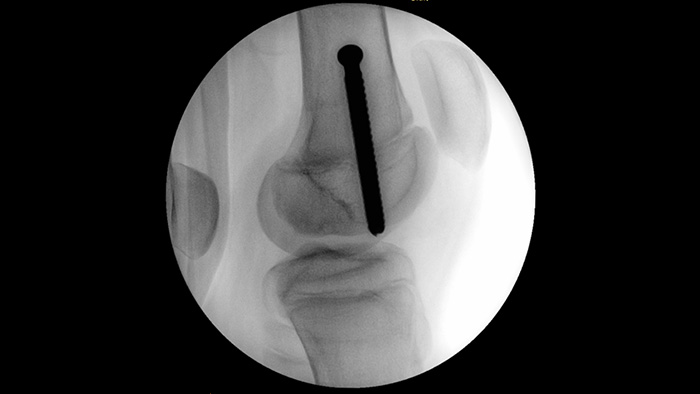

MetalSmart entfernt automatisch Metallartefakte aufgrund von Metallimplantaten und sorgt somit für eine bessere Bildqualität im Vergleich zu Systemen ohne Metallausschluss und für eine effiziente Dosiskontrolle bei orthopädischen Verfahren und Patienten mit Metallimplantaten. BodySmart ermöglicht eine Bildgebung mit auf Anhieb aussagekräftigen Ergebnissen sowie Dosiseffizienz durch die automatische Anpassung des Messfelds an den relevanten Bereich.